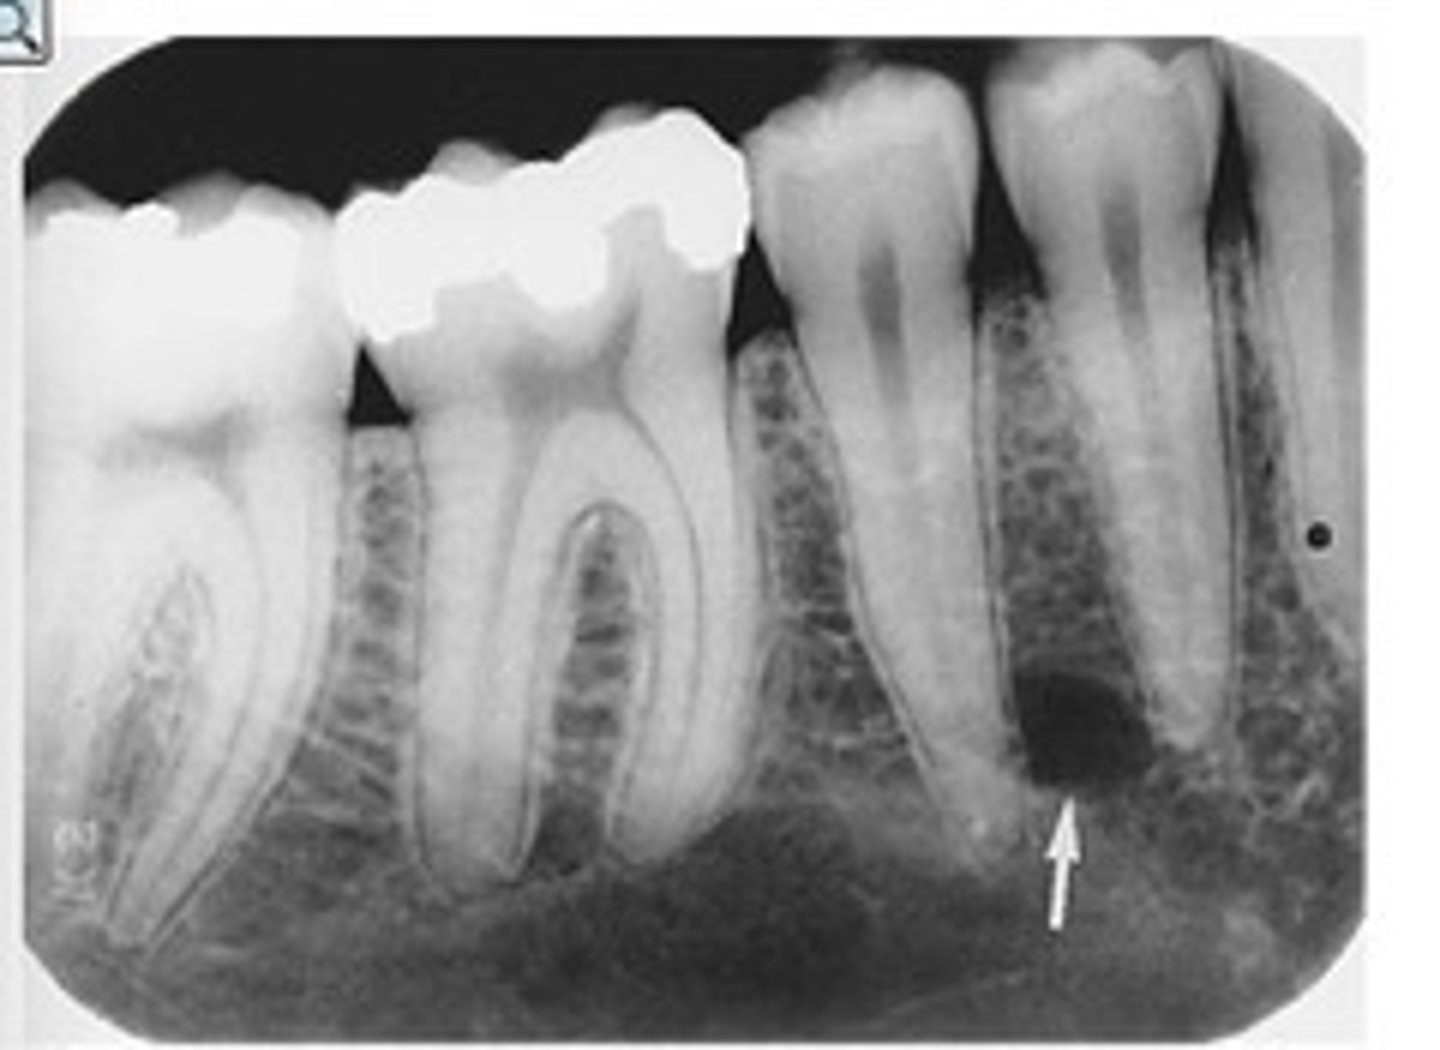

Mandibular canal

What is the radiolucent structure seen here?